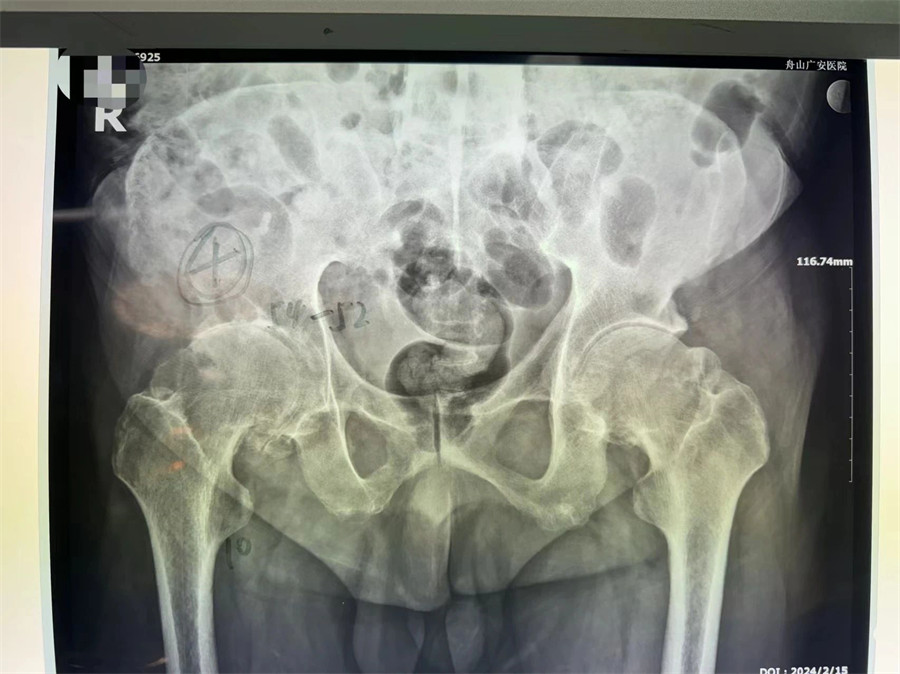

術(shù)前拍片顯示髖關(guān)節(jié)僵直伴股骨頭壞死

羅軍主任分析患者病情,認(rèn)為他強(qiáng)直性脊柱炎30年,雙髖關(guān)節(jié)強(qiáng)直,骨贅增生嚴(yán)重,嚴(yán)重影響行走功能,診斷為強(qiáng)直性脊柱炎,雙側(cè)髖關(guān)節(jié)骨關(guān)節(jié)炎晚期。治療方案只有人工髖關(guān)節(jié)置換這一種選擇。因患者的頸腰椎已經(jīng)完全融合,手術(shù)和麻醉都是一個(gè)不小的挑戰(zhàn),羅軍主任帶領(lǐng)關(guān)節(jié)置換團(tuán)隊(duì)協(xié)同麻醉科團(tuán)隊(duì),經(jīng)過(guò)嚴(yán)密細(xì)致的討論,與患者及家屬充分溝通交流后,決定行機(jī)器人輔助DAA入路全髖關(guān)節(jié)置換術(shù)。機(jī)器人輔助加微創(chuàng)置換,為這項(xiàng)高難度手術(shù)提供了有力支撐。